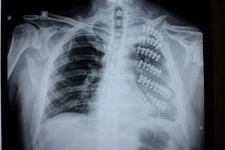

1. KalpKalp, göğüs kafesinin ortasında, kaburga kemiklerinin hemen altında yer alır. Kalp, vücudun kan pompalama işlevini yerine getirir ve dolayısıyla hayati bir organdır. Kaburga kemikleri, kalbi dış etkenlerden koruyarak, onun sağlıklı bir şekilde çalışmasını destekler. 2. AkciğerlerAkciğerler, kaburga kemiklerinin her iki yanında yer alan, solunum sisteminin en önemli parçalarından biridir. Kaburga kemikleri, akciğerleri korurken, aynı zamanda onların genişlemesini ve daralmasını sağlayan bir yapı oluşturur. Akciğerlerin sağlığı, genel sağlık durumu için kritik öneme sahiptir. 3. TrakeaTrakea, hava yollarını oluşturan tüp şeklindeki bir yapıdır ve akciğerlere hava ileten bir kanal vazifesi görür. Trakea, kaburgaların arasında yer aldığından, hava akışını sağlarken bu alandaki diğer organlarla etkileşim içerisindedir. 4. ÖzofagusÖzofagus, yiyecekleri ağızdan mideye ileten boru şeklindeki bir yapıdır. Kaburga kemiklerinin hemen arkasında yer alır ve bu sayede besinlerin mideye taşınmasında önemli bir rol oynar. 5. DiyaframDiyafram, göğüs boşluğuyla karın boşluğunu ayıran kaslı bir yapıdır. Kaburga kemiklerinin alt kısmında yer alarak, solunum sırasında akciğerlerin genişlemesine yardımcı olur. 6. Medastinum OrganlarıMedastinum, göğüs kafesinin ortasında yer alan ve birçok önemli organı içeren bir boşluktur. Thymus, büyük damarlar ve lenf düğümleri gibi organlar bu alanda bulunur. Kaburga kemikleri, bu organların korunmasında önemli bir rol oynar. SonuçKaburga kemikleri, vücut için hayati öneme sahip birçok organı koruyan önemli bir yapıdır. Kalp, akciğerler, trakea, özofagus, diyafram ve medastinum organları, bu yapı içerisinde yer alarak, insan sağlığının sürdürülmesinde kritik bir rol oynar. Kaburga kemiklerinin sağlıklı bir yapıya sahip olması, bu organların düzgün bir şekilde çalışmasını destekler. Ekstra BilgilerKaburga kemikleri, çeşitli sağlık sorunları ve yaralanmalara karşı hassas bir yapıdadır. Kaburga kırıkları, ciddi yaralanmalara neden olabilir ve bu durum, yukarıda bahsedilen organların işlevselliğini etkileyebilir. Dolayısıyla, göğüs kafesi yaralanmalarının önlenmesi ve tedavisi, sağlık açısından büyük önem taşır. |

Akciğerler de kaburgalar tarafından korunmaktadır ve bu durum, solunum sağlığı açısından son derece önemlidir. Kaburgalar, akciğerlerin genişlemesi ve daralması sırasında hareket etmelerine olanak tanırken, aynı zamanda onları dış darbelerden korur. Sağlıklı akciğerler, genel sağlık durumunun bir göstergesi olduğundan, kaburga kemiklerinin durumu da bu bağlamda önem taşır.

Diyafram, solunumda kritik bir rol oynamaktadır. Kaburga kemiklerinin sağlığı, diyaframın düzgün çalışmasını ve böylece solunumun etkili bir şekilde gerçekleşmesini sağlar. Diyaframın kasılması ve gevşemesi, akciğerlerin havayı alıp vermesi üzerinde doğrudan etkilidir.

Mediastinum, kalp, trakea ve özofagus gibi önemli organların bulunduğu bir alandır. Kaburga kemikleri bu bölgedeki organların korunmasında da önemli bir rol oynar. Bu nedenle, kaburgalarda yaşanacak herhangi bir sorun, bu organların işlevselliğini olumsuz etkileyebilir.